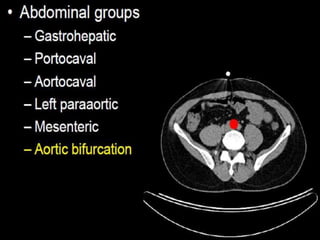

CT cross sectional anatomy.